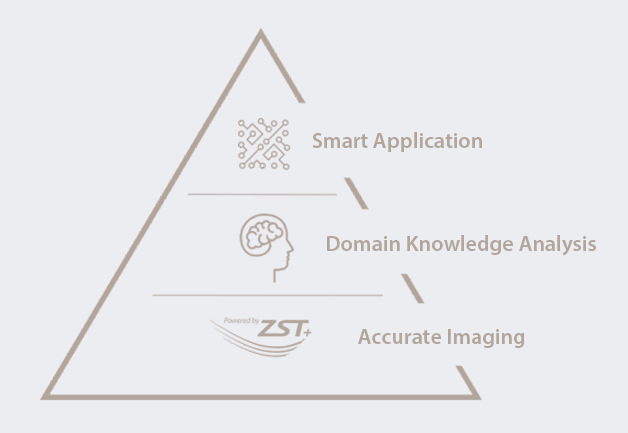

Toplumun geli?mesi ve kad?n sa?l??? sorunlar?na ili?kin endi?elerin artmas?yla birlikte, gitgide daha fazla kad?n, dÞzenli Kad?n Do?um/Jinekoloji ultrason muayeneleri yapt?rman?n ?nemini fark ediyor. Ultrason muayenelerine y?nelik olarak artan talep ku?kusuz sonografi uzmanlar? i?in yeni bir zorluk getirdi, bunun yan?nda, talep gitgide daha fazla segmente ayr?ld?. ?novasyonlar?yla Mindray, sÞreci basitle?tirmek ve daha fazla kad?n?n yÞksek kalitede ultrason te?his hizmetinden yararlanmas?n? sa?lamak Þzere, Zone Intelligence? ile desteklenecek ?ekilde, kad?n ve ?ocuklara y?nelik sa?l?k hizmetleri i?in tam kapsaml? ak?ll? ??zÞmler sunuyor. Gebelik ?ncesi, gebelik, do?um sonras? iyile?me sÞrecinden yenido?anlara kadar bir?ok muayene senaryosunun Þstesinden gelmeleri, b?ylelikle kad?n ve ?ocuklar?n sa?l?klar?n? korumalar? i?in, sonografi uzmanlar?n? âsihirli bir silahâ ile gÞ?lendirmeyi umuyoruz.

Kad?n ve ?ocuklara Y?nelik Sa?l?k Hizmetleri i?in Zone Intelligence? ile Desteklenen Tam Kapsaml? Ak?ll? ??zÞmler

Smart Pelvic